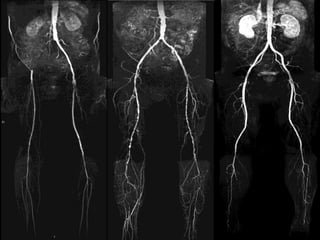

 -Angiography

- Arteriography

Arteriography

1- Laboratory investigations: 2-Imaging:  - Doppler flow study. ABI Segmental pressure  - Duplex scanning  -Angiography

1- Laboratory investigations: 2-Imaging: - Doppler flow study. • ABI • Segmental pressure - Duplex scanning - Arteriography Arteriography